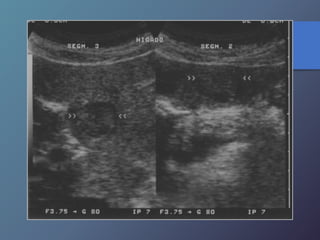

Cirrosis Hepática

Proceso difuso hepático caracterizado

por fibrosis y la conversión de la

arquitectura normal del hígado en

nódulos estructuralmente anormales.

• Redistribución de volumen. Índice

caudado/lob. Der. 0.65.

• Ecoestructura grosera.

• Superficie nodular.

• Nódulos de regeneración.

• Nódulos displásicos.

• Hipertensión portal: Ascitis, esple-

nomegalia, varices.

Características Ecográficas